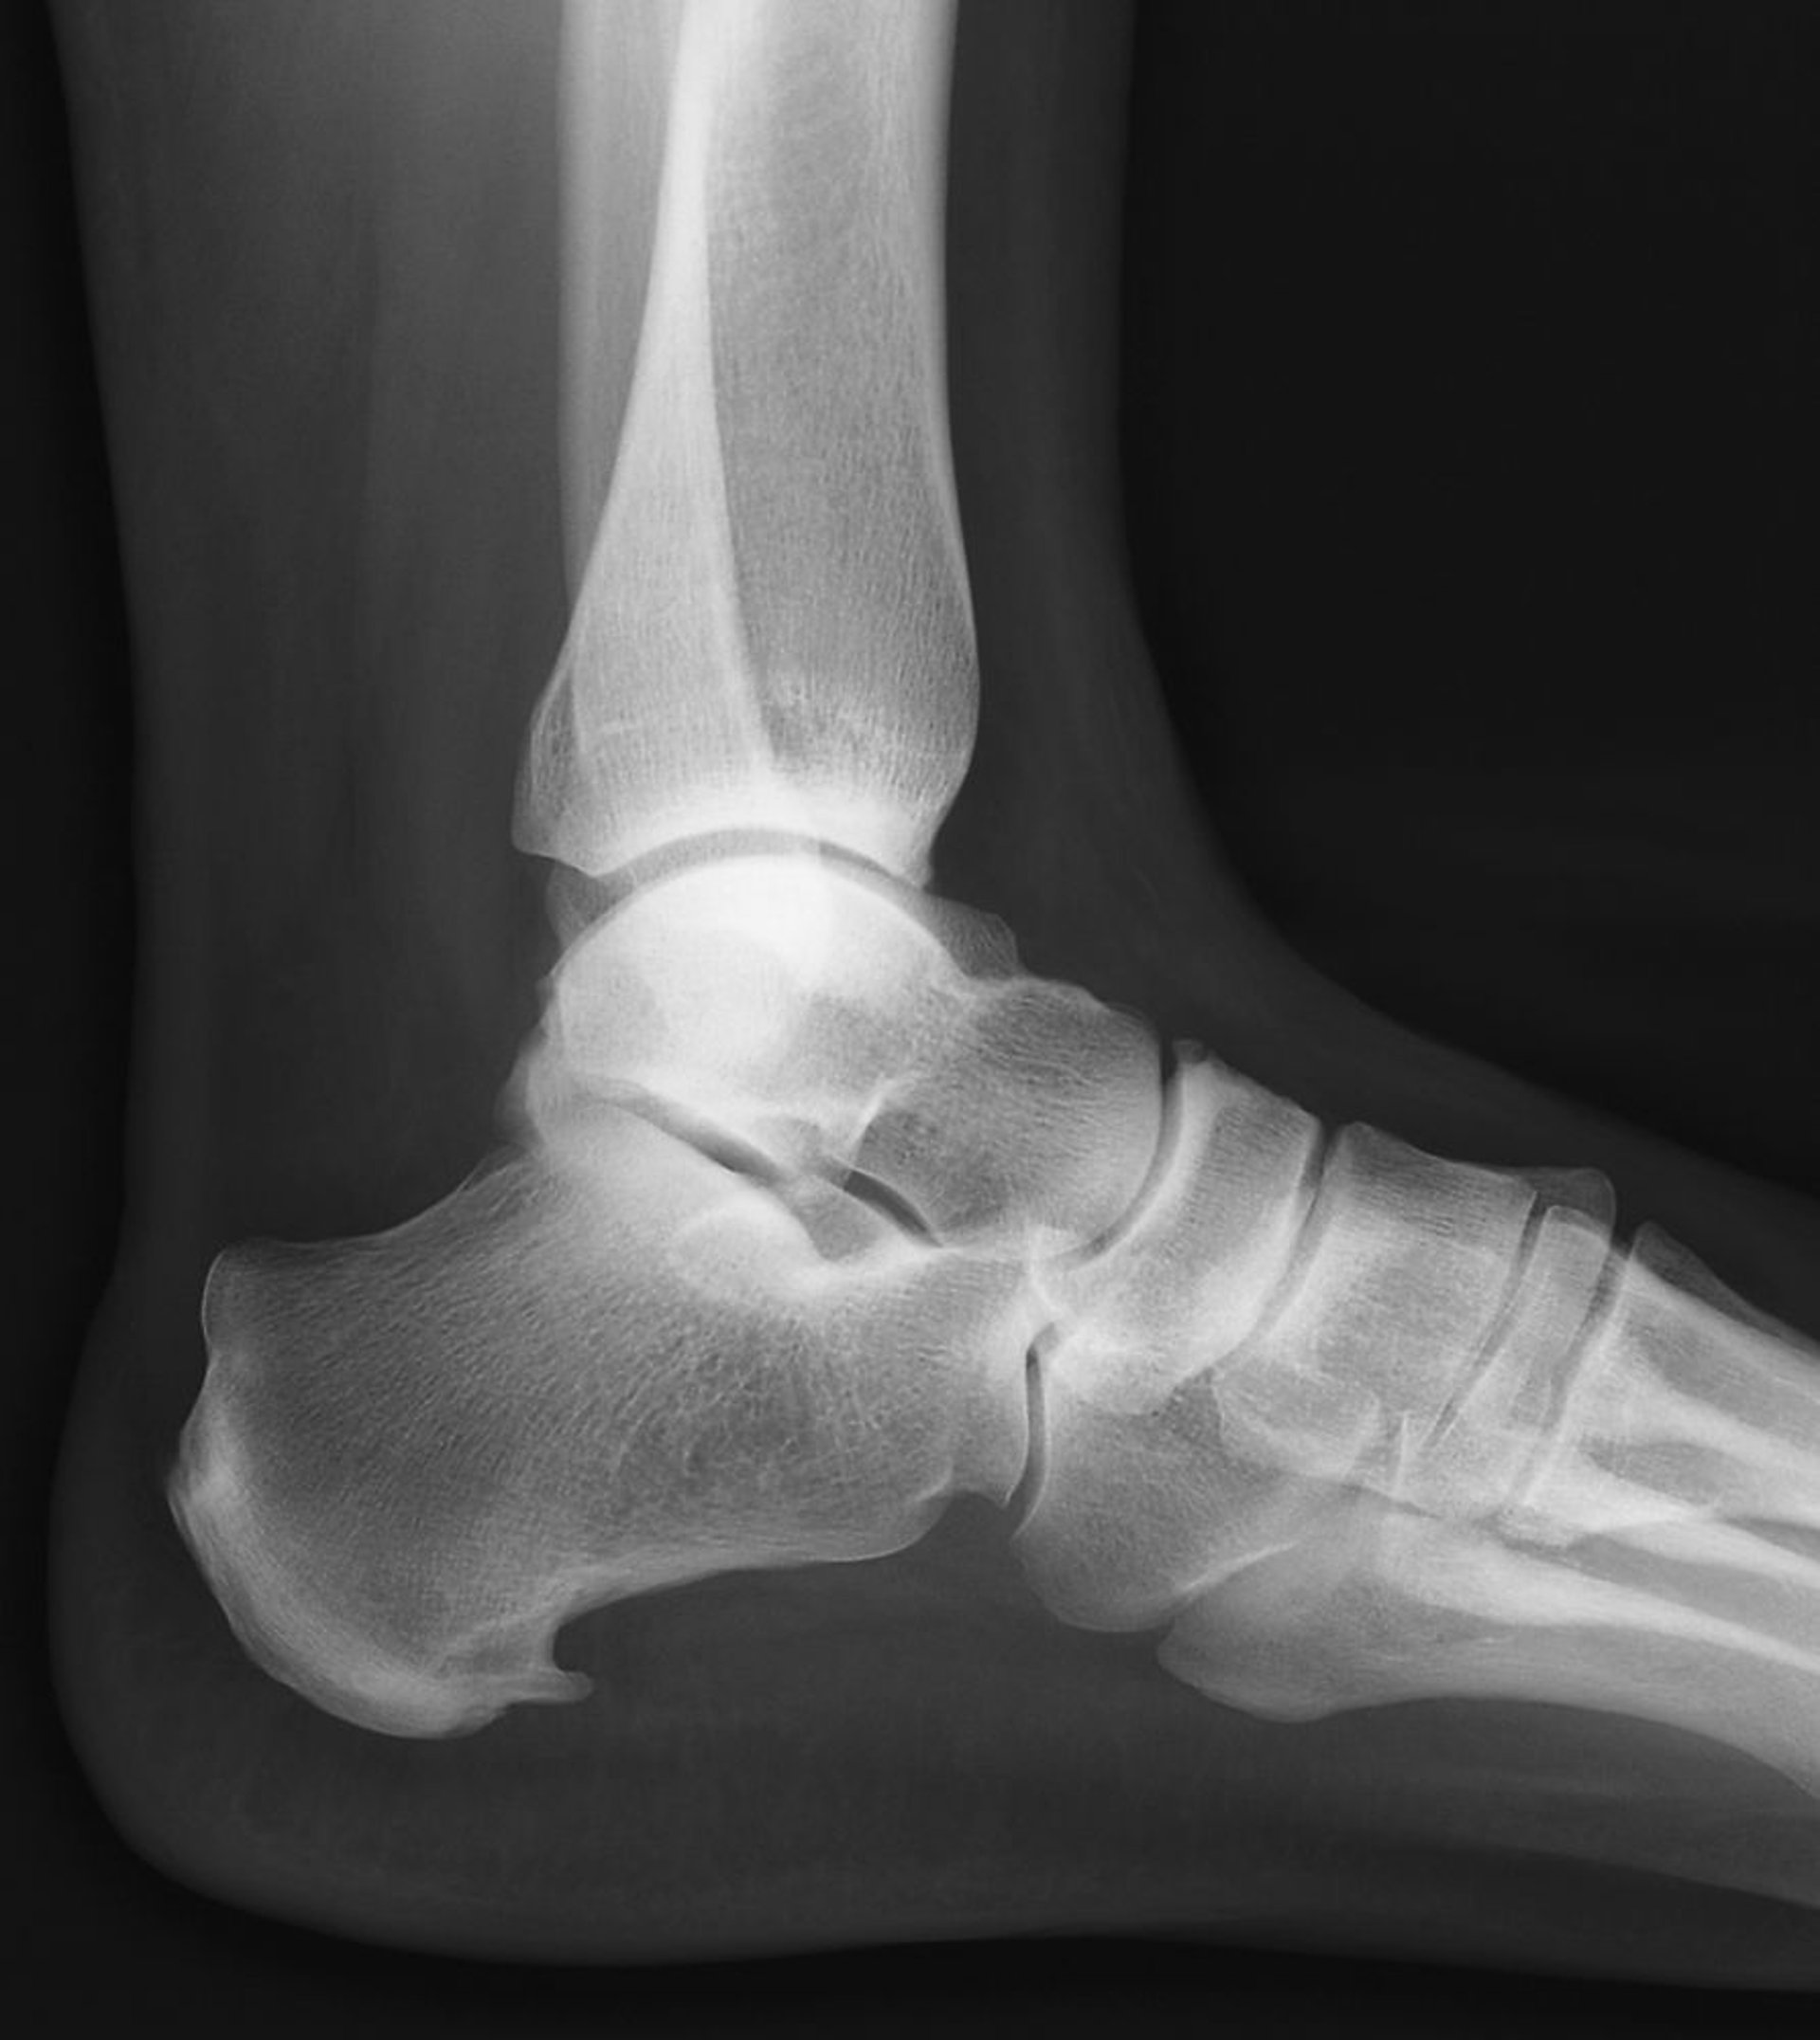

Der Fersensporn ist die knöcherne Exostose, die sich an der Unterseite des Kalkaneus nach vorne erstreckt.

ZEPHYR/SCIENCE PHOTO LIBRARY